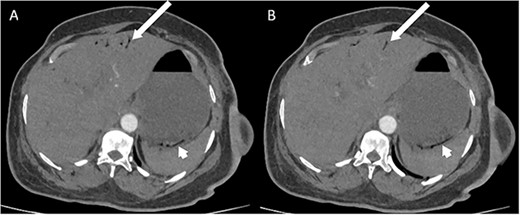

Whilst awaiting her planned orthopaedic surgery, the patient developed epigastric and retrosternal chest pain on Day 13 of admission, associated with persistent vomiting and abdominal distension. On examination, she had a moderately distended abdomen, with no focal peritonism present. Initial blood tests performed showed mildly elevated inflammatory markers, normal serum troponin levels, and a raised D-dimer. As such, a computed tomography (CT) pulmonary angiogram was initially performed; whilst no evidence of pulmonary embolism was identified, an incidental finding of gas within the liver peripheries (Fig. 1A) and the gastric fundal wall was noted (Fig. 1B). A subsequent plain film abdominal radiograph performed showed a significantly distended stomach (Fig. 2).

CT pulmonary angiogram images demonstrating moderate amount of branching linear gas in the liver (long arrows), most pronounced in (A) at the level of T11/12; gas within the wall of the gastric fundus (short arrows) can be appreciated more in (B) at the level of T11.